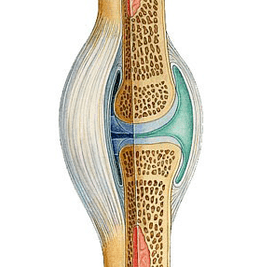

Wirkmechanismus des Gels Icexin

Aktion Icexin aufgrund der Eigenschaften der in seiner Zusammensetzung enthaltenen Komponenten. Beim Auftragen auf die Haut in der Projektion des betroffenen Gelenks dringen die Wirkstoffe in das darunter liegende Gewebe ein und üben eine lokale Wirkung auf die Hauptglieder des pathologischen Prozesses aus. Das Produkt hilft, die Schwere der Schmerzen zu reduzieren, die Mikrozirkulation zu verbessern und die Elastizität des Knorpelgewebes zu erhalten.

Im Gegensatz zu systemischen Formen, die zur oralen Verabreichung vorgesehen sind, gewährleistet das externe Gel die Abgabe der Komponenten direkt an den Beschwerdenbereich. Dadurch können unerwünschte Auswirkungen auf den gesamten Körper minimiert werden. Icexin kann sowohl in Phasen der Verschlimmerung der Symptome von Arthritis oder Arthrose als auch als Mittel zur Vorbeugung bei erhöhter Belastung eingesetzt werden.

- Erhaltung der Knorpelstruktur. Glucosamin und Chondroitin sind Substrate für den Aufbau von Bindegewebe.

- Normalisierung des Gelenktrophismus. Eine erhöhte Mikrozirkulation verbessert die Ernährung des Gefäßknorpels.